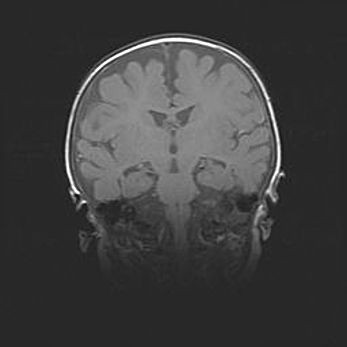

Наружная гидроцефалия с возможной атрофией височных областей.

Возраст: 28 дней

Вес: 3670 г

Пол: мужской

Окружность головы: 38 см

Срок гестации: 40 недель

Гидроцефалия головного мозга у новорожденных – это заболевание, которое характеризуется скоплением избыточного количества спинномозговой жидкости в желудочковой системе головного мозга в результате затруднения её перемещения от места выработки к месту поглощения в кровеносную систему или вследствие нарушения абсорбции. При открытой наружной форме гидроцефалии у новорожденных расширяются и переполняются субарахноидные пространства.

При нормотензивных  формах,  которые,  как  правило,  являются  следствием  перенесенных ишемических  повреждений  паренхимы  мозга,  возможно  сочетание микроцефалии  с нормотензивной гидроцефалией. В основе данных изменений лежит атрофия больших полушарий с преимущественной  локализацией  в  лобно-височных  областях.